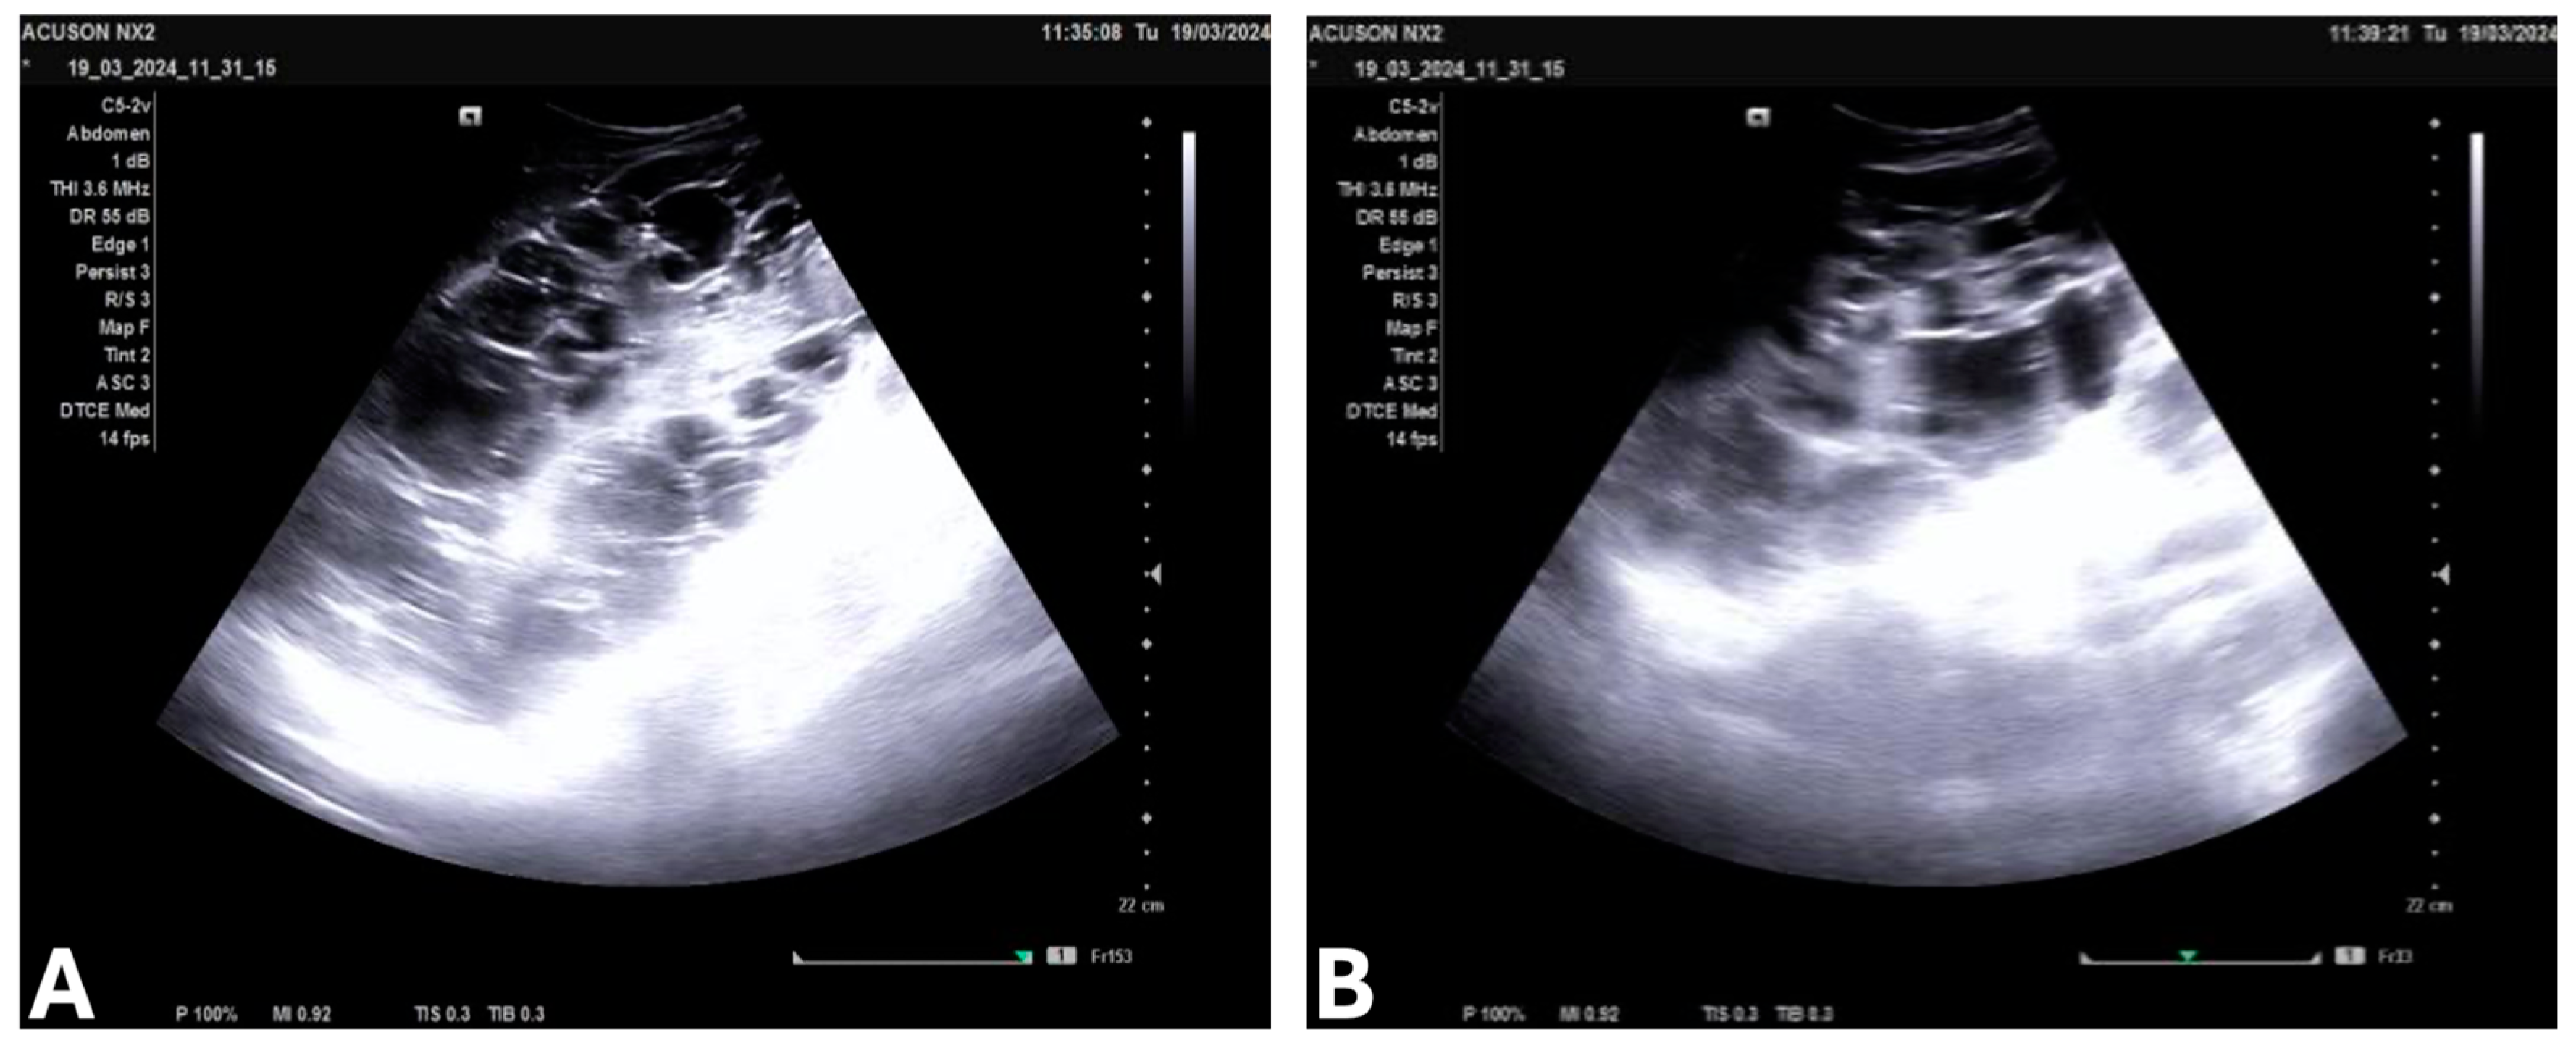

3.4. Laboratory Findings, Imaging, and Stage of ADPKD